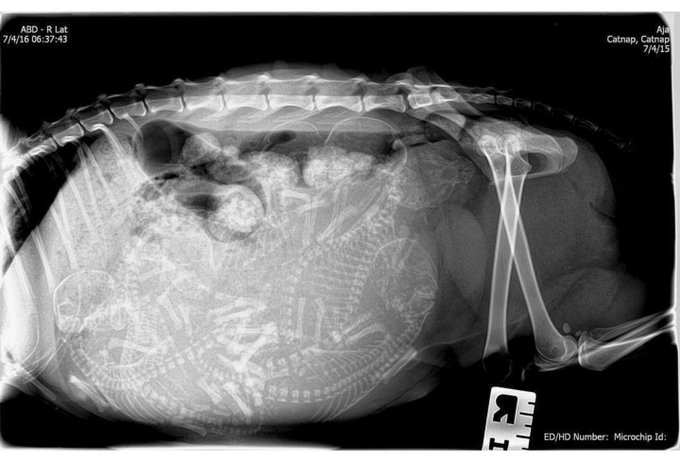

Беременная кошка.